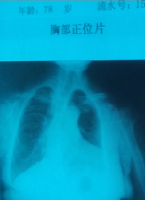

【明慧网二零一六年一月三日】我年近八十岁,在今年的体检中竟意外发现左肺少了一半多(见图)。医生拿着我的X光胸透照片来回的看,反复检查对照测试的设备,还疑惑的询问我是否以前肺部做过手术?

在我表示从未动过肺部手术之后,医生愕然了,按照常规理论,这样的肺是有生命危险的,可我身体反应和精神状态并无异常,医生的检查结论无法下笔了。